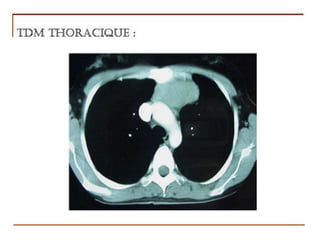

II. Diagnostic positif

II.2. Éléments du Diagnostic

2-2-Examen Paraclinique – Noninvasifs

2.2.1.1. Imagerie thoracique

b) TDM thoracique avec injection de

produit de contraste

permet de caractériser la masse

de visualiser ses relations avec les

structures avoisinantes, d’identifier la

composition de la masse (kyste, tissu

,graisse, vaisseau)

permet également la meilleure

approche en vue de la biopsie diagnostic

2.2.1.1. TDM thoracique avec injection

b) Imagerie thoracique                       de

permet aussi de mieux visualiser les

calcifications

= EXAMEN suffisant pour l'exploration

des masses du médiastin antérieur et

moyen. (Dans la majorité des cas)

2.2.1.1. Imagerie thoracique b) TDM thoracique

Les caractéristiques TDM des masses médiastinales

avec injection

peuvent se résumer en quelques points :

tissulaire:

   masse homogène, hyperdense,

ronde, ovalaire ou tubulaire

    avec une paroi bien définie,

   rehaussant après injection de produit de

contraste

Kystique:

   masse densité liquidienne(0 à 20 UH ;

   pas d'infiltration adjacentes.

   Pas de rehaussement

Graisseuse= densité négative